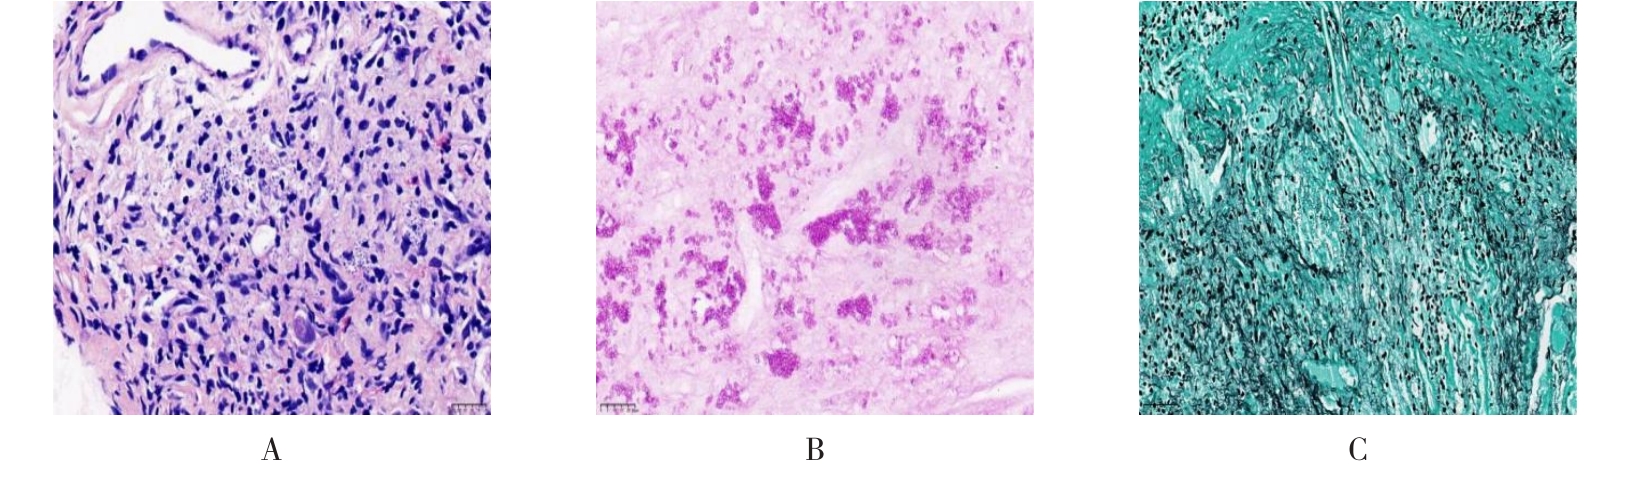

摘要:目的 探讨获得性免疫缺陷综合征(AIDS)合并马尔尼菲篮状菌(TM)感染导致肠道感染的内镜下特征。方法 回顾性分析2022年11月-2024年10月于该院确诊为AIDS合并TM感染导致肠道感染的6例患者的临床资料。包括:临床症状、实验室检查、影像学检查、内镜检查和病理检查等。结果 6例患者中,男5例,女1例;发病年龄26~67岁;AIDS合并TM感染导致肠道感染患者的临床表现为:腹泻、腹痛、腹胀和恶心呕吐。其中,2例有消化道出血表现。实验室检查:6例患者外周血白细胞计数为(1.37~4.49)×109/L,血红蛋白计数为(67~99)g/L;CD4+T淋巴细胞为(1~52)个/μL,CD8+ T淋巴细胞为(61~321)个/μL,CD4+T淋巴细胞/CD8+T淋巴细胞比值为(0.01~0.18)。6例患者均行HIV RNA检测。其中,5例HIV RNA阳性。血培养:可见丝状真菌,报告显示为TM。影像学检查:6例患者CT结果可见肠系膜及腹膜后多发淋巴结肿大。内镜检查:6例患者内镜下均可见肠道病变。其中,十二指肠糜烂溃疡2例,结肠多发糜烂溃疡4例。病理检查:6例患者幽门螺杆菌(Hp)结果均为阴性,黏膜下可见成簇的小球形真菌孢子,符合TM感染;特殊染色:PAS(+),六胺银染色(+)。结论 当AIDS晚期患者出现消化道症状时,应警惕TM感染,病变部位常见于全结肠和直肠,亦可累及十二指肠,内镜下表现多为溃疡、糜烂和隆起性病变,形态表现无特异性;及时行胃肠镜检查、病理活检、特殊染色和免疫组化是确诊的关键。